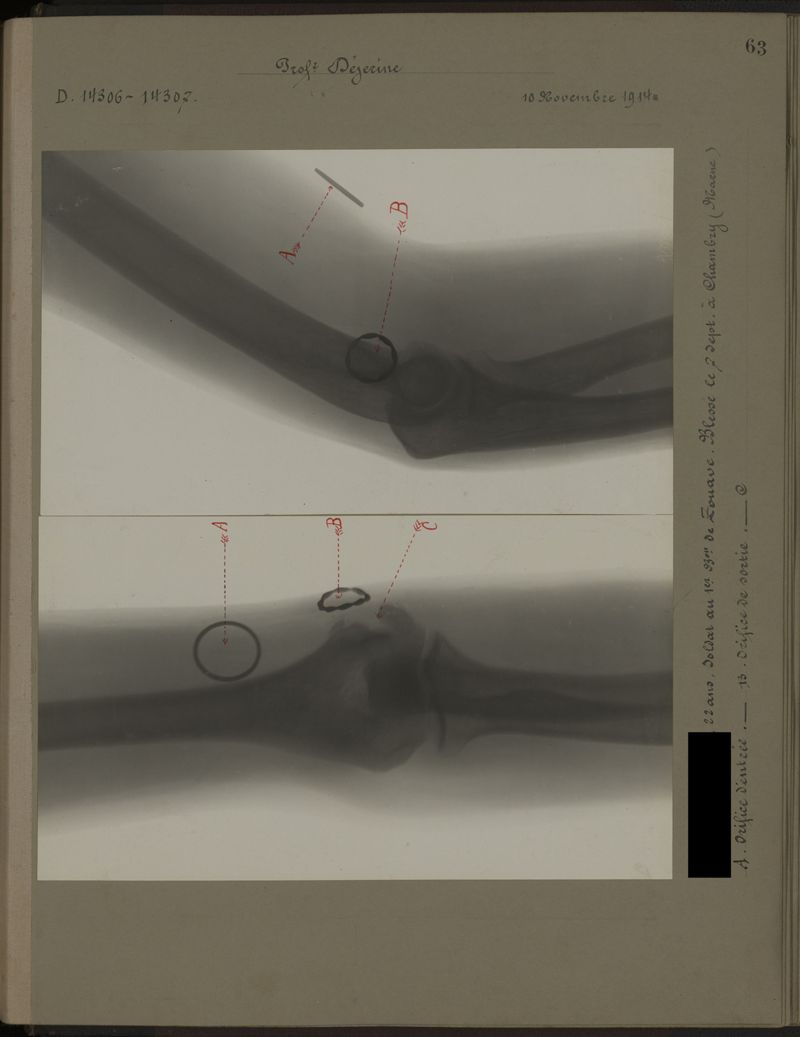

Deux albums de radiographies de la Première Guerre mondiale. Collection du laboratoire central de radiographie de la Salpêtrière. Deuxième album.

1915.